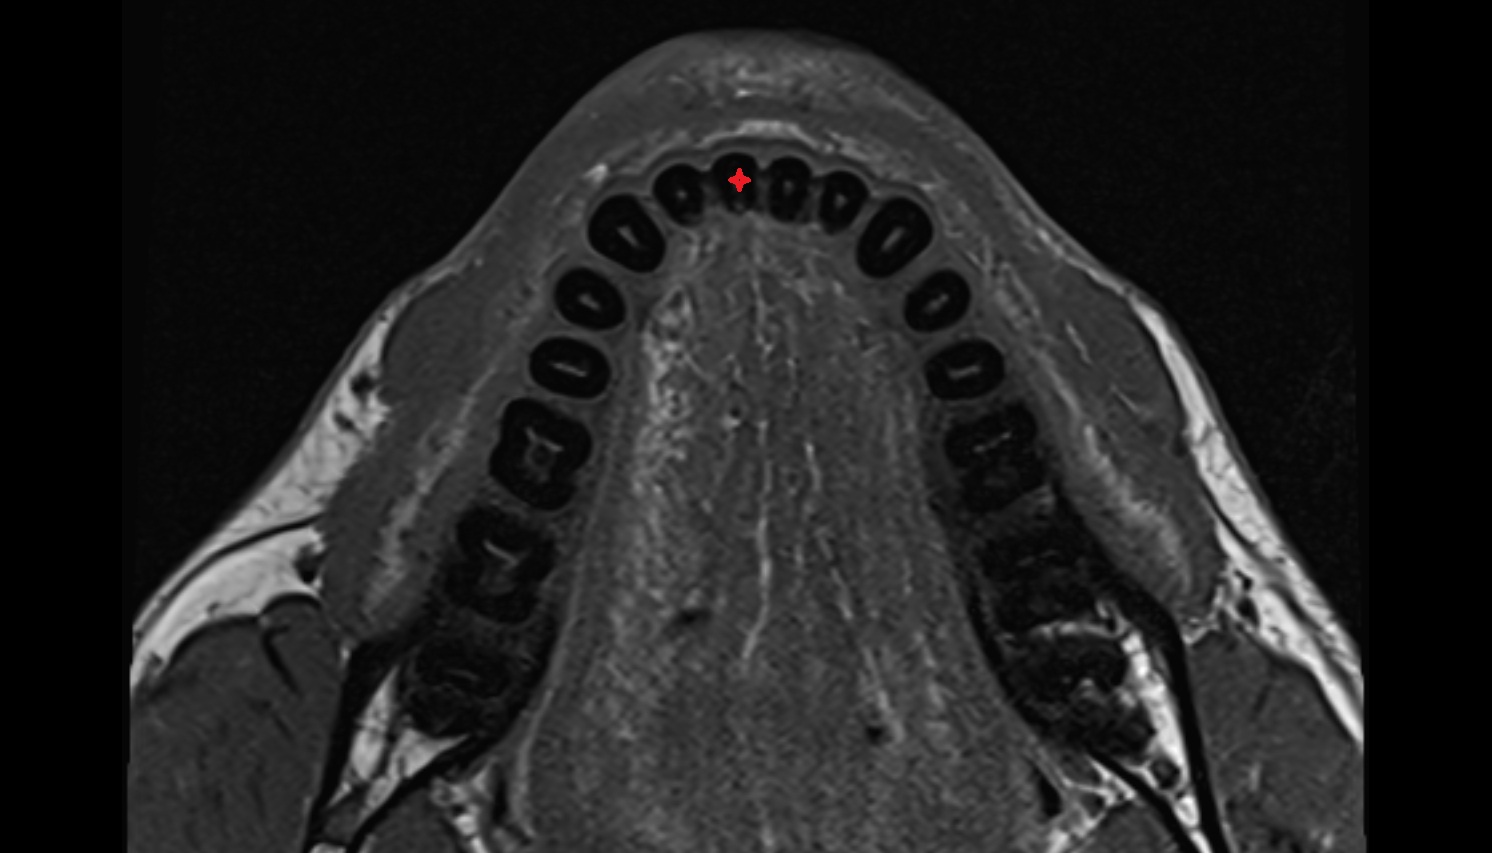

- Central inferior incisor tooth

- Central superior incisor tooth

- Inferior canine tooth

- Lateral inferior incisor tooth

- Lateral superior incisor tooth

- superior canine tooth

- Superior first molar tooth

- Superior first premolar tooth

- Superior second molar tooth

- Superior second premolar tooth

- Superior third molar tooth